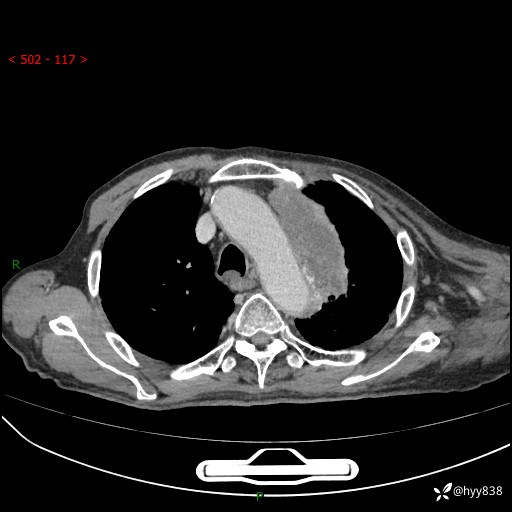

老年男性,气促5月,胸背痛2月。发现肺尖较大肿块,摧枯拉朽之势---结果公布~

现病史:患者于5月前饮酒后突发静息状态下气促不适,无胸闷、胸痛、发热、咳嗽、咳痰等不适,于当地第五人民医院及我院就诊,输液治疗后(具体不详)后气促稍缓解,遂出院后自行口服中草药治疗。近2月出现胸背痛,伴左上肢疼痛、乏力、感觉异常,稍有咳嗽、咳痰,咳黄痰、痰液粘稠,无咳血。为进一步诊治来我院。

胸部CT增强扫描(外院平扫)